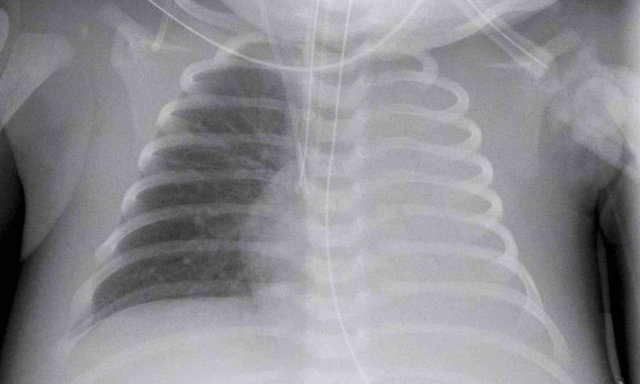

A full term neonate, with respiratory distress after 24 hours.

Image

Hyperinflation of both lungs and cardiac enlargement with increased interstitial markings and vascular markings. No pleural fluid.

The differential diagnosis includes TTN and neonatal pneumonia. After 48 hours there was no improvement of the respiratory distress, and the neonate developed signs of infection.

One might argue that there could be a combination of TTN and pneumonia.